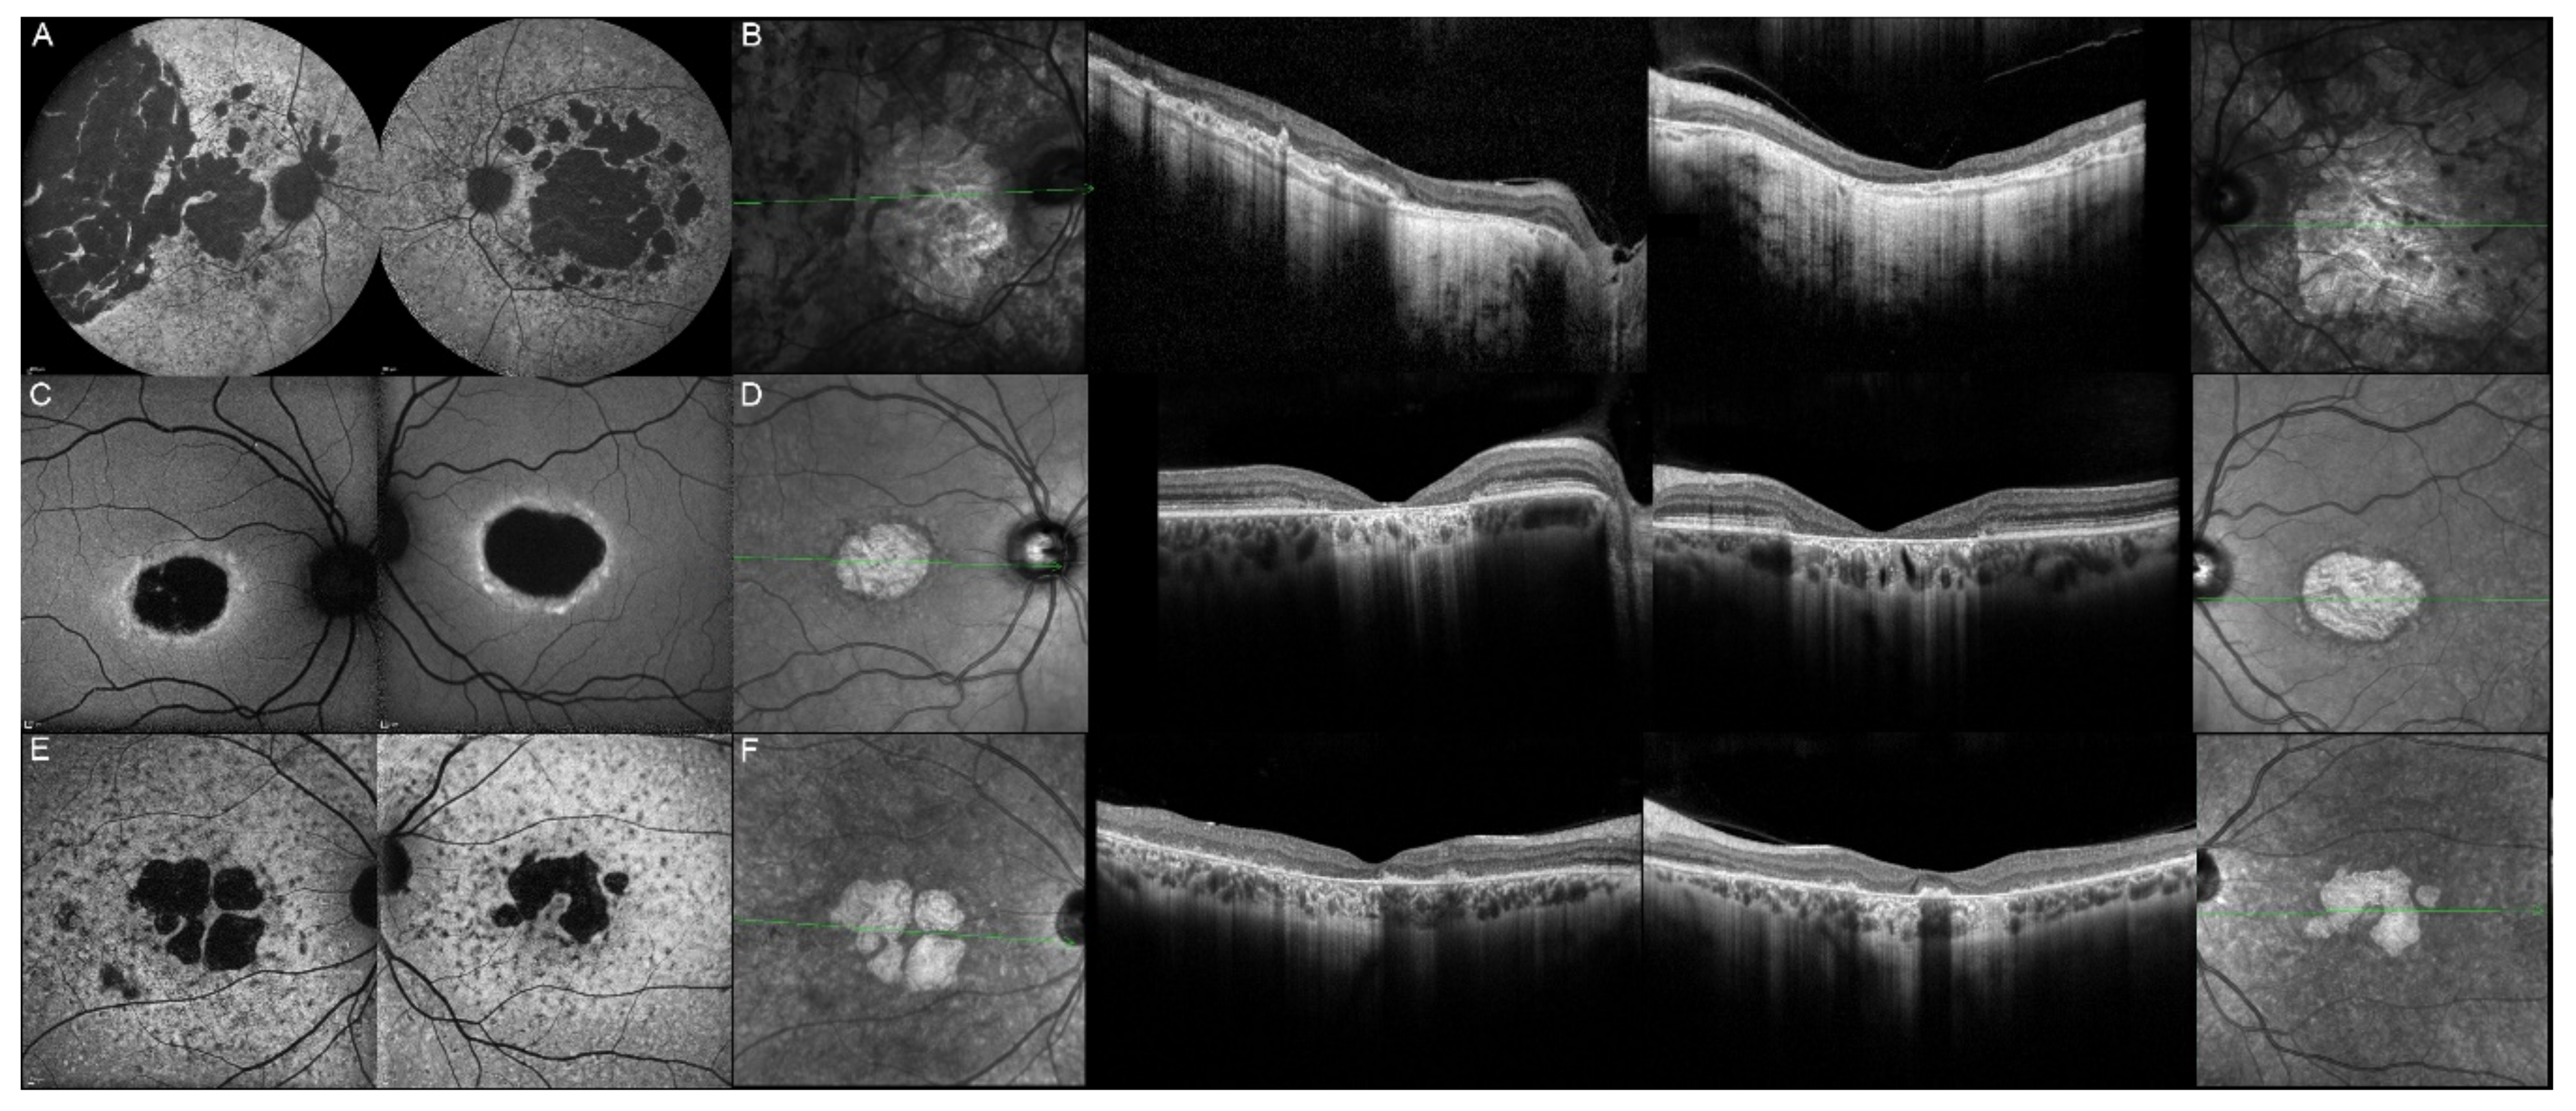

| Patient | Gene | Age | Sex | FAF | OCT |

|---|---|---|---|---|---|

| 1, II.2 | ABCA4 | 53 | F | Foveal HPAF | Subretinal hyperreflective deposits |

| 2, II.1 | ABCA4 | 18 | F | Central HOAF; concentric ring of HPAF | Central EZ disruption with gap; ONL atrophy |

| 3, II.2 | ABCA4 | 18 | F | Foveal HOAF; central mottled pattern of HPAF and HOAF flecks | Central EZ loss; central ONL atrophy |

| 4, II.2 | ABCA4 | 27 | F | Foveal HPAF; parafoveal HOAF; paramacular HPAF | Central EZ loss; central ONL atrophy |

| 5, II.2 | ABCA4 | 69 | F | Mid-peripheral mottled HOAF | Mid-peripheral ONL atrophy, lamellar macular hole (OD) |

| 6, II.2 | ABCA4 | 53 | F | Foveal HOAF; central mottled pattern of HPAF and HOAF flecks | Central EZ disruption with gap (OS) and loss (OD); central ONL atrophy |

| 7, II.1 | ABCA4 | 19 | F | Central HOAF; HPAF flecks | Central EZ loss; central ONL atrophy |

| 8, III.2 | ABCA4 | 30 | M | Central HOAF; HPAF flecks | NA |

| 9, II.2 | ABCA4 | 44 | F | Central mottled pattern of HPAF and HOAF flecks | Central EZ loss; central ONL atrophy |

| 10, I.2 | ABCA4 | 51 | F | Foveal HOAF; central mottled pattern of HPAF and HOAF flecks | Perifoveal EZ loss; perifoveal ONL atrophy; loss of the foveal depression |

| 11, III.1 | ABCA4 | 53 | M | Extended central and peripheral HOAF; panretinal diffuse mottled pattern of HPAF and HOAF flecks | ONL atrophy; peripheral choroidal atrophy; RPE atrophy; subretinal hyperreflective deposits |

| 12, II.2 | ELOVL4 | 37 | F | Central HOAF; concentric ring of HPAF | Central EZ loss; central ONL atrophy and RPE atrophy |

| 13, II.1 | ELOVL4 | 46 | F | Multifocal areolar parafoveal HOAF; mottled pattern of HPAF and HOAF flecks; perimacular to mid-peripheral HPAF flecks | Perimacular EZ loss; perimacular ONL atrophy; subretinal hyperreflective deposits |

| 13, III.2 | ELOVL4 | 19 | F | No special features | Subfoveal hyperreflective deposits (OD) |

| 13, III.1 | ELOVL4 | 21 | M | NA | No special features |

| 13, I.1 | ELOVL4 | 82 | M | Areolar HOAF; paracentral mottled pattern of HPAF and HOAF flecks | ONL thinning; perimacular localised EZ loss (OS) |

| 14, II.4 | ELOVL4 | 48 | M | Central mottled pattern of HPAF and HOAF flecks | Central EZ loss; central ONL atrophy; perimacular subretinal hyperreflective deposits |

| 15, II.3 | ELOVL4 | 34 | M | Subfoveal HOAF; concentric ring of HPAF | Central EZ disruption with gap; central ONL atrophy |

| 16, III.2 | ELOVL4 | 28 | F | NA | NA |

| 17, II.1 | PRPH2 | 51 | F | Butterfly pattern of HPAF and HOAF flecks; paramacular to mid-peripheral HPAF flecks | Irregular EZ thickening |

| 18, II.2 | PRPH2 | 69 | M | Subfoveal HOAF (OS); butterfly pattern of HPAF and HOAF flecks; paramacular to mid-peripheral HPAF flecks | Central EZ loss (OS); central ONL atrophy (OS); localised ONL thinning (OD) |

| 19, III.2 | PRPH2 | 39 | F | Central areolar HOAF; disseminated nummular HPAF | Extended retinal atrophy |